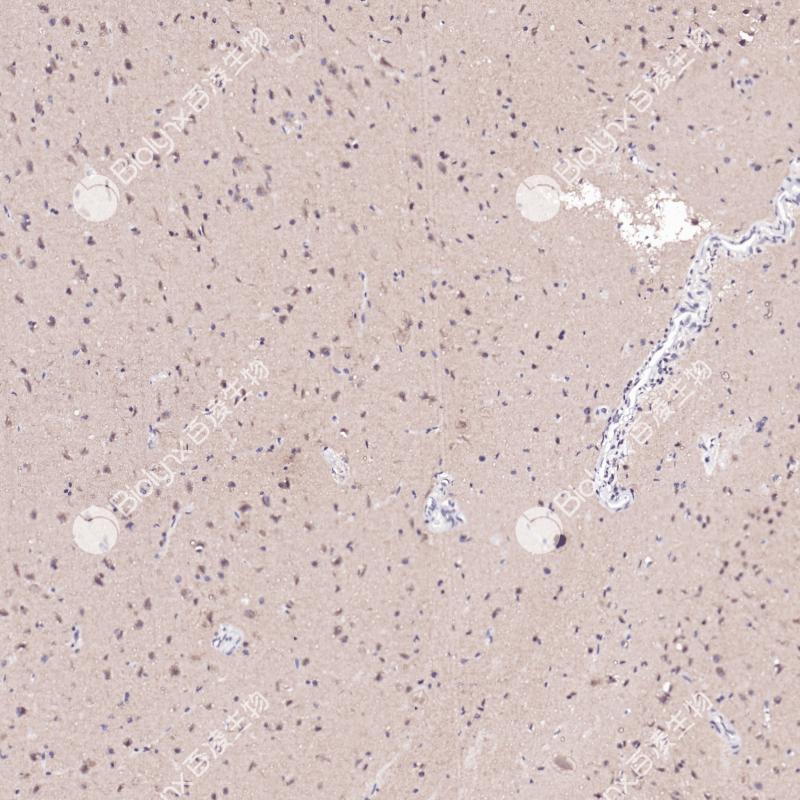

阳性对照

乳腺癌

亚细胞定位

细胞核